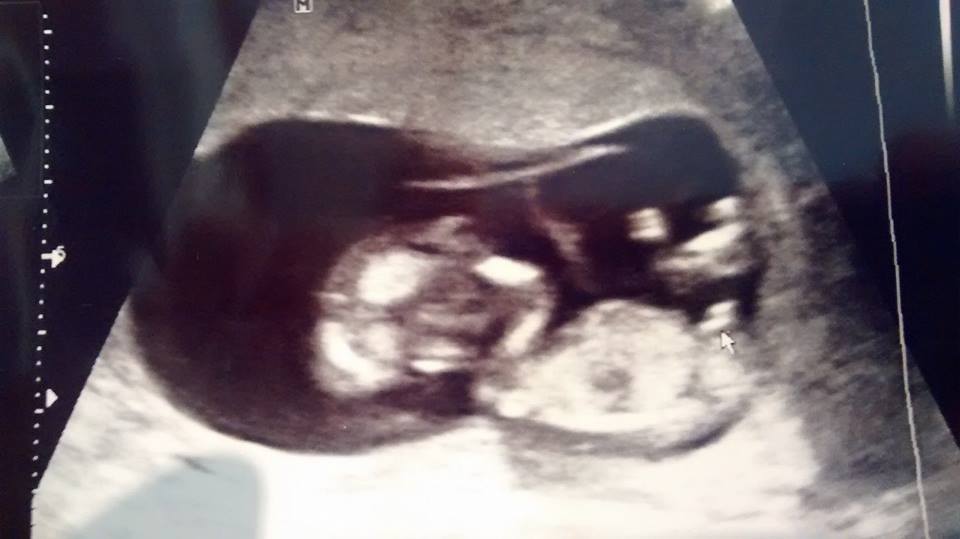

Had my 12 week US yesterday and the tech was pretty positive on her guess. I'm wondering what you ladies think. Thanks in advance!

I think I got a super nub shot! Any guesses? '07 '07 '09 '09 '11 '11

Boy boy boy   7 7

Haha. It really is something I haven't seen before. I yelled 'WHAT?!?!' In the tech's face because she said a word I've never heard in an ultrasound before. Still kind of in shock. Lol. Can't wait to confirm...  '07 '07 '09 '09 '11 '11

April 24th, 2014, 09:18 PM #8Congratulations on your boy